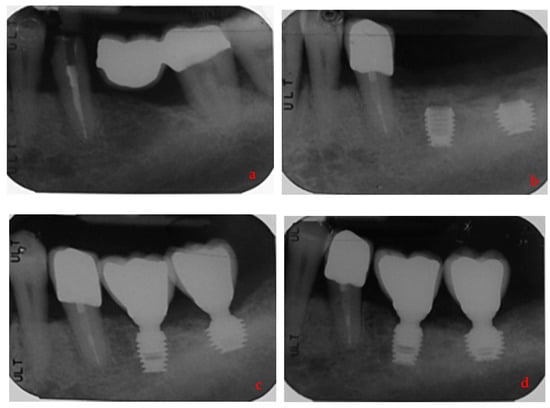

- Lombardo, G.; Signoriello, A.; Simancas-Pallares, M.; Marincola, M.; Nocini, P.F. Survival of Short and Ultra-Short Locking-Taper Implants Supporting Single Crowns in the Posterior Mandible: A 3-Year Retrospective Study. J. Oral Implant. 2020, 46, 396–406. [Google Scholar] [CrossRef] [PubMed]

- Lombardo, G.; Marincola, M.; Signoriello, A.; Corrocher, G.; Nocini, P.F. Single-Crown, Short and Ultra-Short Implants, in Association with Simultaneous Internal Sinus Lift in the Atrophic Posterior Maxilla: A Three-Year Retrospective Study. Materials 2020, 13, 2208. [Google Scholar] [CrossRef] [PubMed]